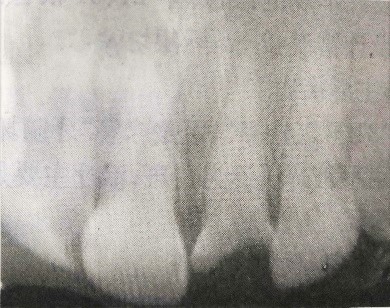

檢查:21牙冠缺損,黑褐色,根管口暴露,覆蓋污穢物,探診(-),冷測(cè)(-),叩診(+)。左上1唇側(cè)牙齦根尖部有白色瘺管出現(xiàn)。X線片檢查提示:21根尖區(qū)低密度影。全口牙齦紅腫,探診后出血,且下頜后牙區(qū)有附著喪失。相關(guān)情況請(qǐng)見下圖: